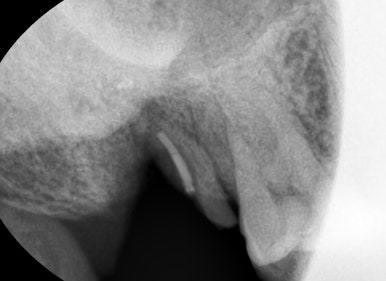

오래된 신경치료한 치아의 뿌리가 부러져서 환자가 악취가 나고 아프다고 방문 → 발치

만약 신경치료한 치아를 씌우지 않아 뿌리부분이 두 동강나거나 파절된다면 살릴 수 없어

발치하는 경우가 많게 됩니다.

신경치료를 하고 난 후 크라운을 하지 않고 방치하여 깨진치아 → 꺠진 부위가 머리부위라 크라운을 하여 해결